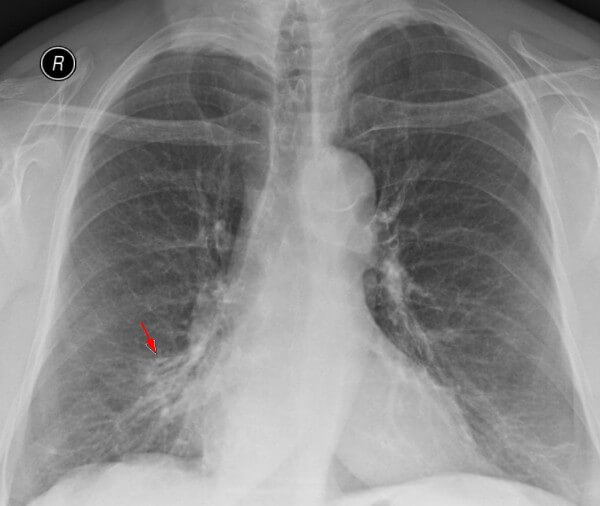

Самым распространенным методом диагностики легких является – флюорография. Но если врач подозревает, что у пациента есть спайки, то больной отправляется на рентген. По рентгеновскому снимку распознать синехию можно по мутным темным пятнам. Она выглядит, как теневое затемнение и неподвижна при вдохе и выдохе.

Плевродиафрагмальная спайка на снимке рентгена

Иногда выявляется деформация грудной клетки и диафрагмы. Чаще всего спаечный процесс отмечается в нижней части легкого. Такой вид спаек – плевродиафрагмальный, а вид спаек в верхней части – плевроапикальный.

Для обнаружения легочных заболеваний в первую очередь используется флюорография. Эту процедуру необходимо проводить ежегодно, в основном она направлена на выявление ранней стадии туберкулеза. Однако опытный рентгенолог может выявить на снимке образовавшиеся плевральные спайки, которые выглядят тенями. Причем форма их не меняется в зависимости от вдоха и выдоха.

При необходимости дополнительно назначается рентген. Как правило, спайки располагаются в нижней части легкого. При этом будет более темная картинка, а также может быть частичная деформация грудной клетки и диафрагмы.